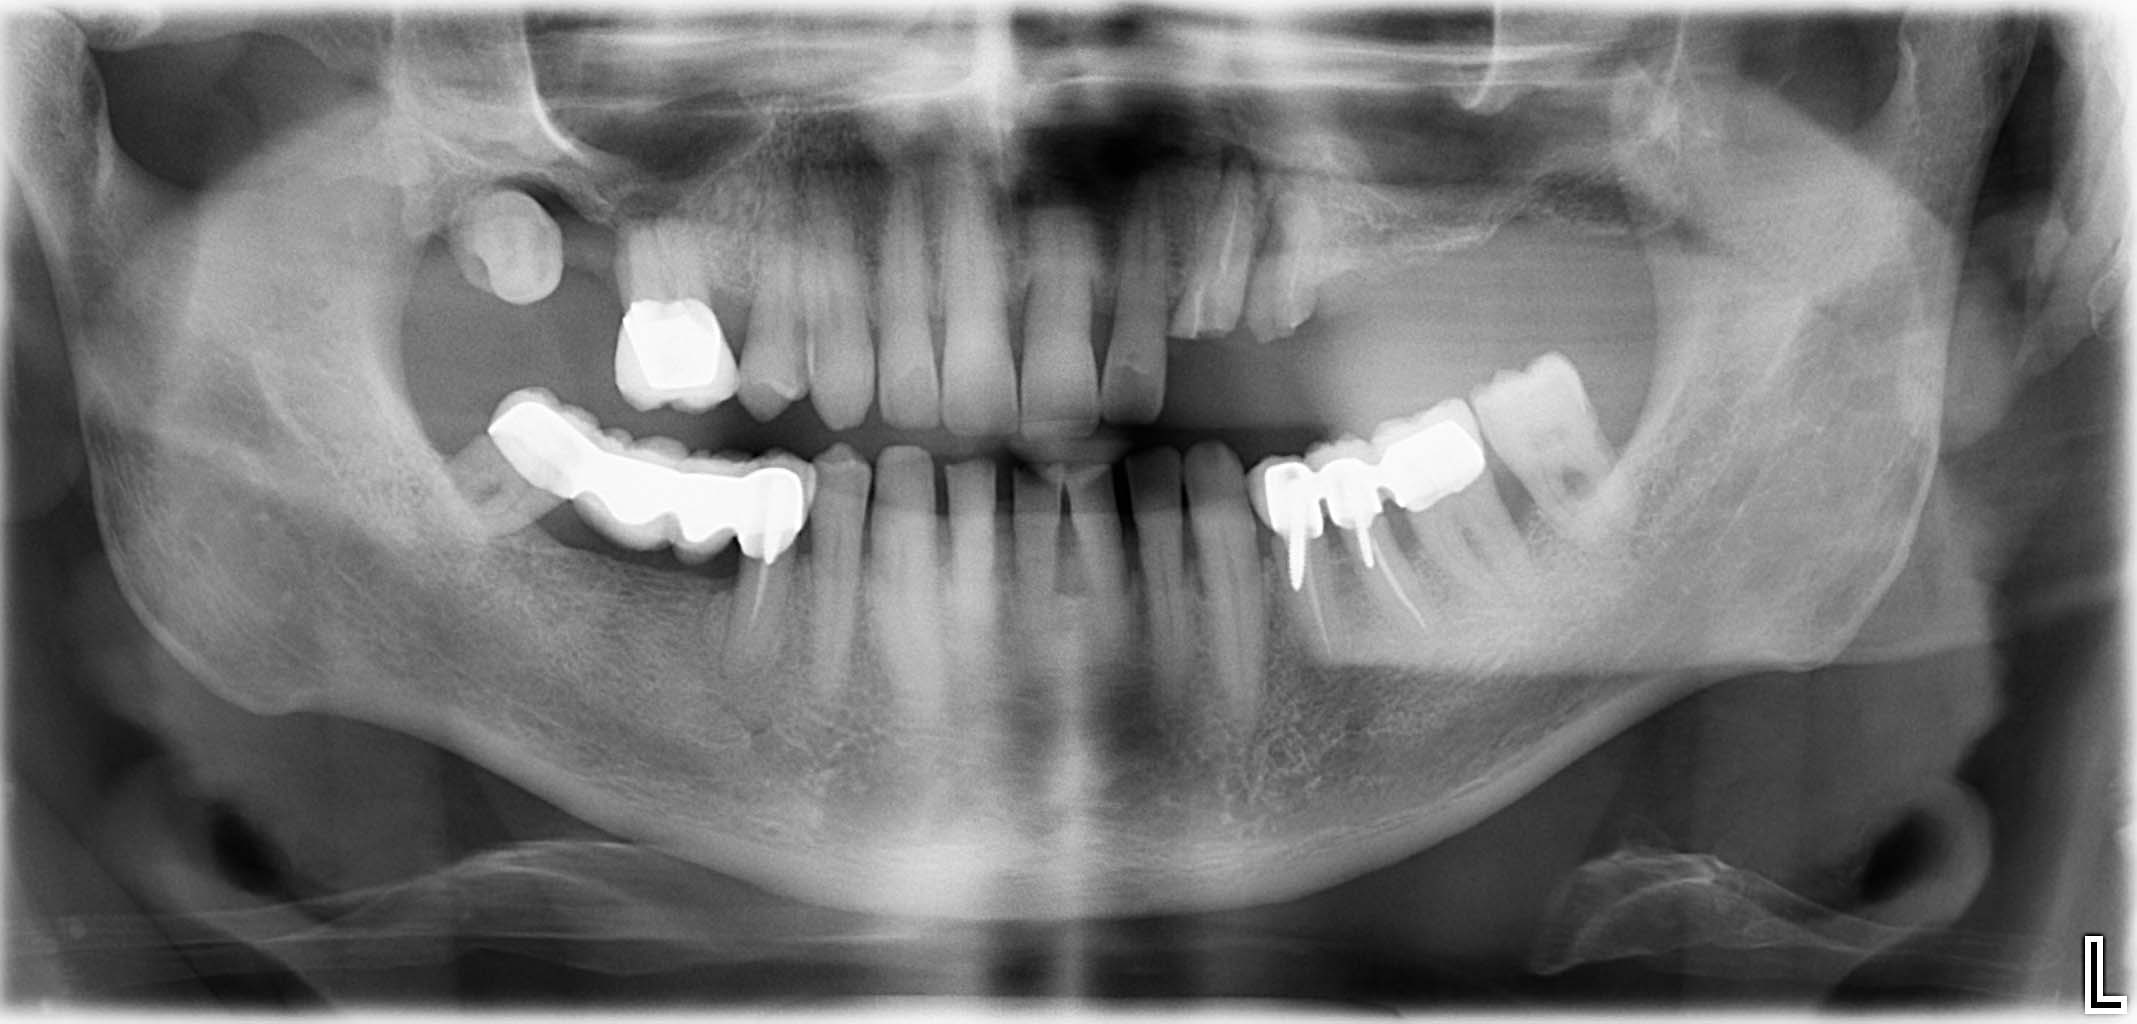

Ausgangssituation: Zahn 36 mit apikaler Beherdung, nicht erhaltungswürdig